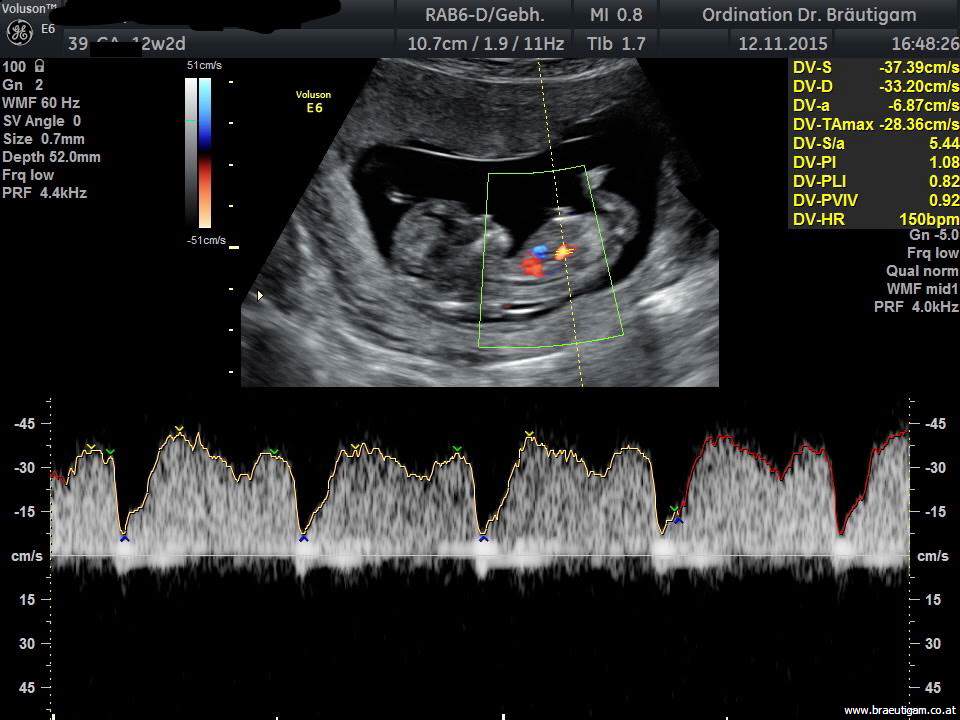

Der Combined Test berechnet das Trisomie-(Down-Syndrom)-Risiko aus:dem Alter der Mutterder Nackentransparenz Bestimmung von freiem ß-HCG und PAPP-A im Blut der Mutter Ultraschall in der 13.-14.Woche

Bei diesem Ultraschall wird die fetale Nackentransparenz (NT) gemessen, das ist eine Flüssigkeitsansammlung unter der Nackenhaut des Feten. Alle Kinder haben etwas Flüssigkeit unter der Haut, und bei Feten mit Down-Syndrom ist diese Flüssigkeit häufig vermehrt.